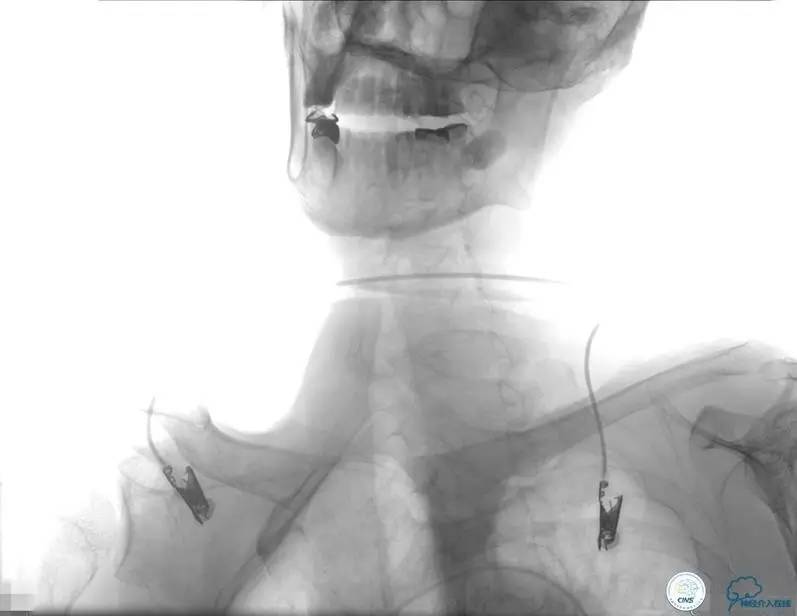

患者时间窗内,发病3h开始静脉溶栓。rt-PA9mg/kg,70mg,7mgIV;63mg微量泵注入1h。期间患者症状改善不明显。观察时间后,仍无改善。遂介入交接治疗。

2015-06-05脑血管造影:左侧颈内动脉闭塞。